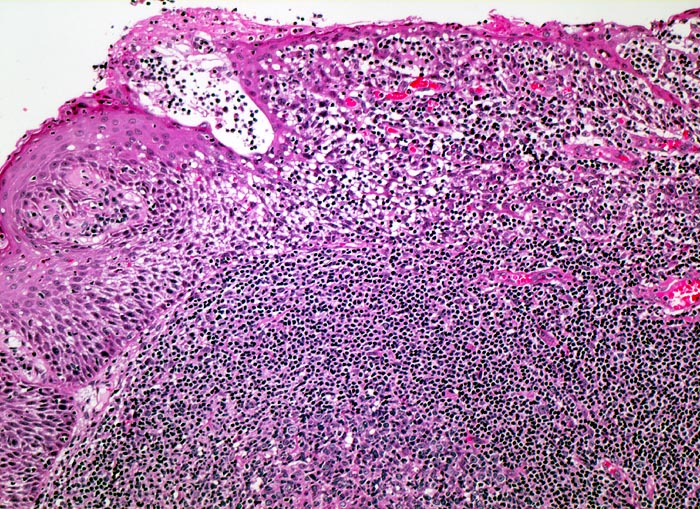

Lymphknoten, lymphatisches Gewebe des Oropharynx und Tonsillen zeigen ähnliche Veränderungen:

• Aktivierung der B-Lymphozyten-Areale (EBV induzierte polyklonale Infektion und Stimulation der EBV-Rezeptor tragenden B-Zellen): grosse, aktivierte Keimzentren (=follikuläre Hyperplasie), aktive parafollikuläre Plasmazellbildung (B-Immunoblasten, Plasmoblasten, Plasmazellen).

• Aktivierung der interfollikulären T-Zone (= sogenannte bunte Pulpahyperplasie) mit Hodgkin-artigen Zellen (= reaktive/aktivierte B- resp. T-Lymphozyten).

• Interfollikuläre Hyperplasie der T-Zone (bunte Pulpahyperplasie):

Hodgkinartige Zellen (=reaktive/aktivierte B- resp. T-Lymphozyten), kleine Lymphozyten, Immunoblasten mit zentralem Nukleolus und Plasmazellen.